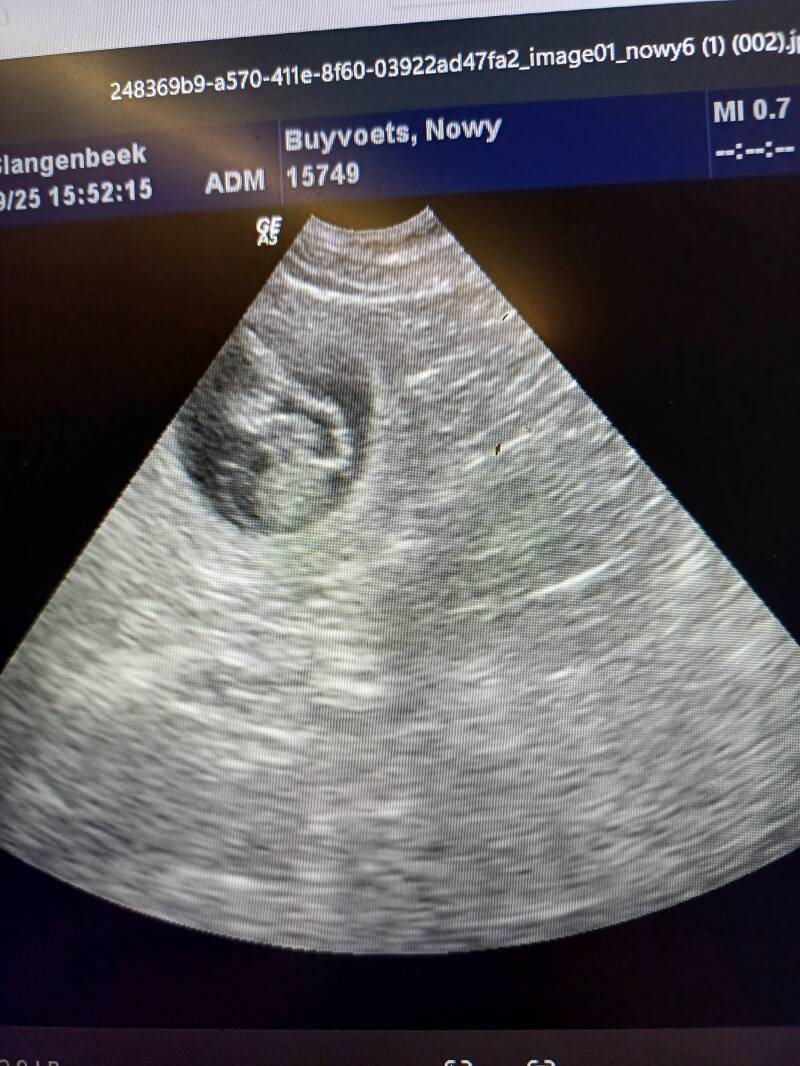

Nowy bijna 6 weken zwanger...haar buikje groeit💕

We zijn net terug van de dierenarts...de echo wees uitlaten er pupjes onderweg zijn van Nowy en Elron.

We hopen ze rond 24 oktober 2025 te verwelkomen